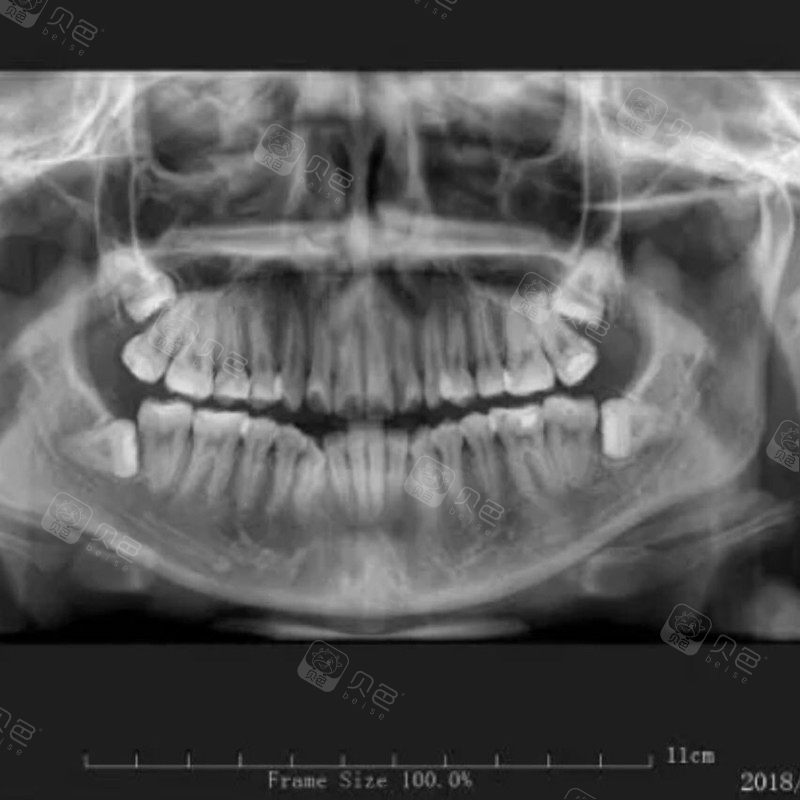

牙片鉴赏|不痛也没有任何感觉但是歪掉的牙可以不拔吗?

牙齿全景片

全景牙片